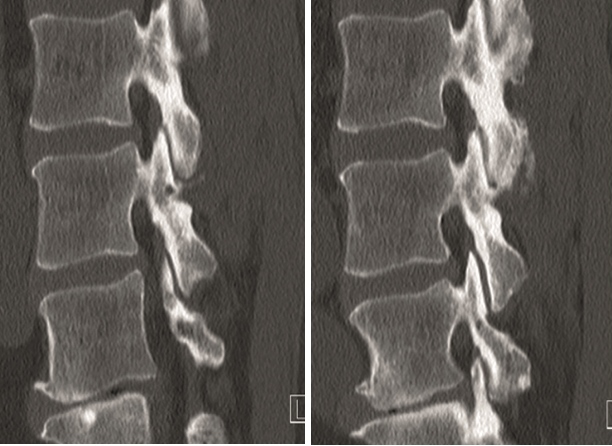

Multilevel facet pathology is shown in Fig 6. Intraoperative and postoperative images are shown (Fig 7-9).